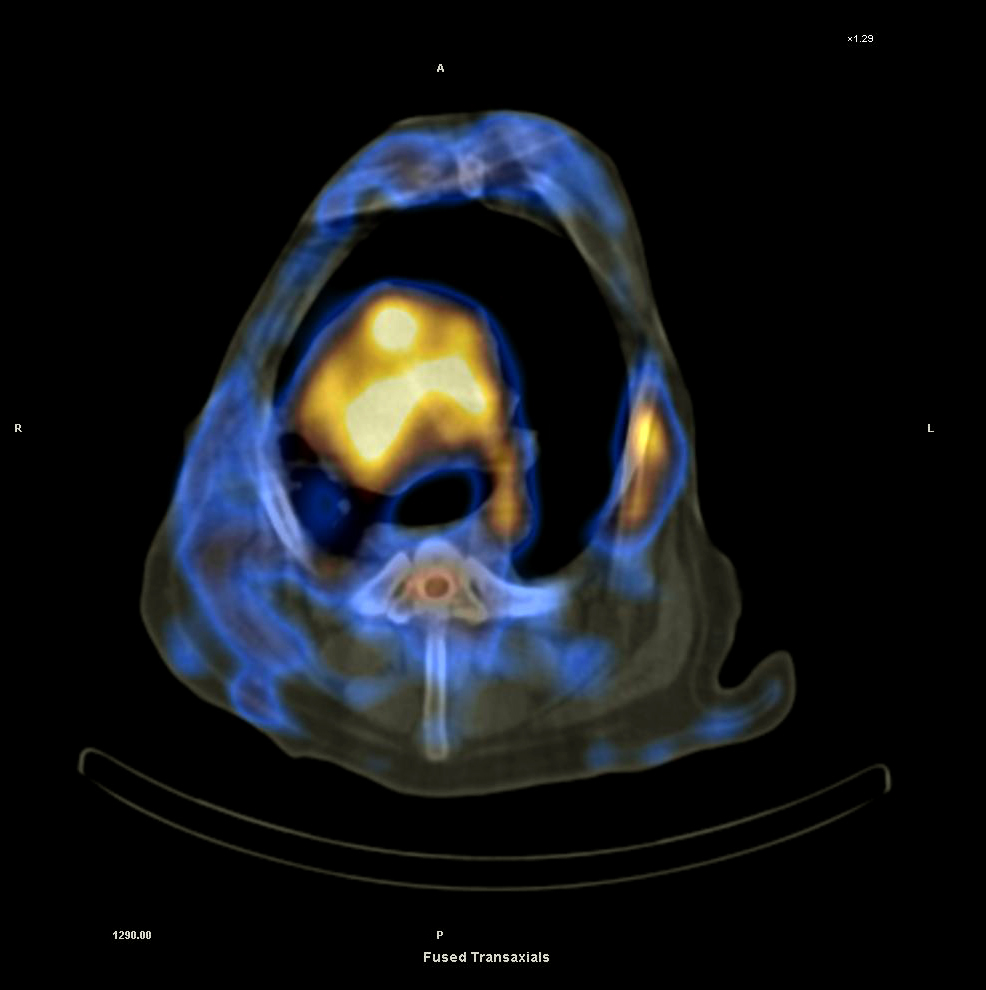

北里大学獣医学部の附属小動物診療センターにおいて、わが国で初となる犬と猫のための「核医学施設」がオープンし、PET診断が実施できるようになった。“動物に優しいがん治療”など、新たな動物医療技術の開発を目指しており、国際的にも先進的な獣医療施設になることが期待されている。

青森県十和田市にキャンパスがある北里大学獣医学部の附属小動物診療センターにおいて、わが国初となる犬と猫のための「核医学施設」がオープン。PET診断が実施できるようになった。

同大獣医学部では、今回の省令改正と同時に青森県に届出を行い、青森県と農林水産省の施設検査を受けた。同大では、すでに動物を対象とする「高精度放射線治療装置」を用いたがん治療を実施しているが、今回の核医学施設の稼働によって、がんの早期診断と放射線治療による“動物に優しいがん治療”など、新たな動物医療技術の開発を目指す。